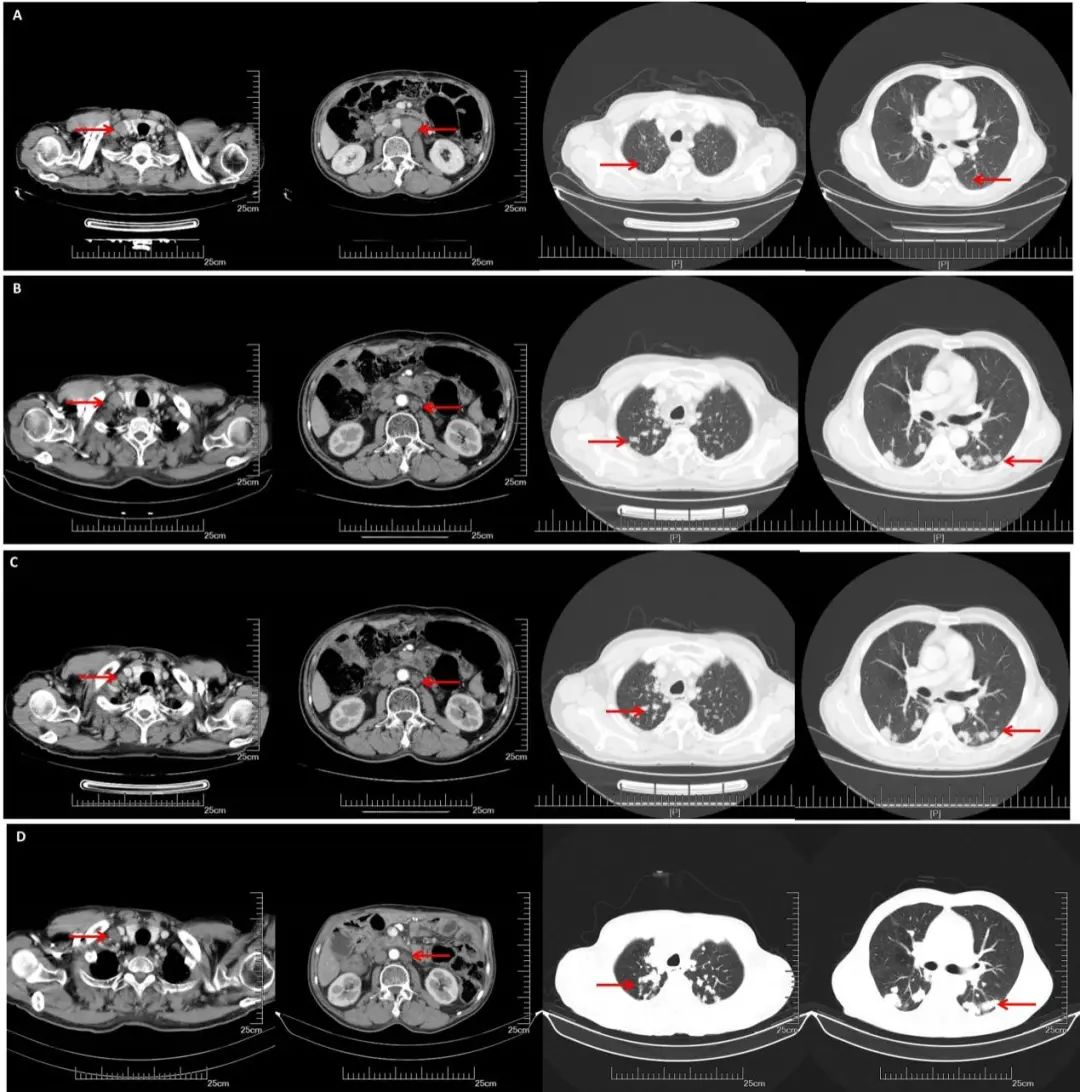

A:CT增强(2018.11.07): 腹膜后多发淋巴结转移,部分较前增大。双侧锁骨上淋巴结转移,部分较前增大,双肺多发结节,转移可能;B:CT增强(2019.05.16):腹膜后淋巴结较前缩小,双肺转移较前增多增大;C:CT增强(2019.10.25):腹膜后淋巴结稳定,双肺转移较前增多增大;D:CT增强(2020.05.27):双肺转移瘤及腹腔淋巴结总体稳定。